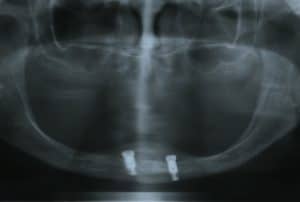

Comparison of the accuracy of implant position for two-implants supported fixed dental prosthesis using static and dynamic computer-assisted implant surgery: A randomized controlled clinical trial. Clin Impl Dent Rel Res 2020

Patient Reported Outcome Measures (PROMs) and maintenance events in 2‐implant supported mandibular overdenture patients: A five‐year prospective study. Clin Oral Impl Res 2018

Peri-implant marginal bone loss rate pre- and post-loading: An exploratory analysis of associated factors. Clin Oral Impl Res 2019